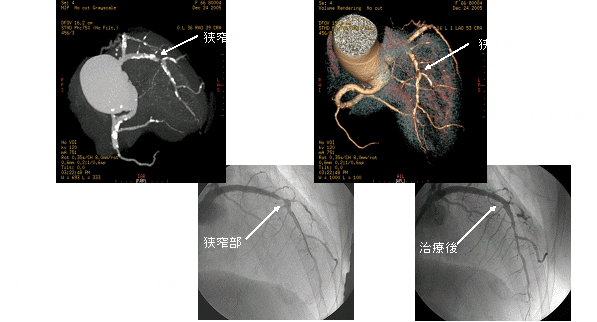

このボリュームCTにより早期発見から早期治療へつなげることが可能となり、心臓カテーテル検査の代替としても期待されます。

一部の症例以外では、従来の心臓カテーテル検査なしに血管狭窄の評価が可能であり、万が一、心筋梗塞になられた場合でも治療後の経過観察の心臓カテーテル検査は不要となります。